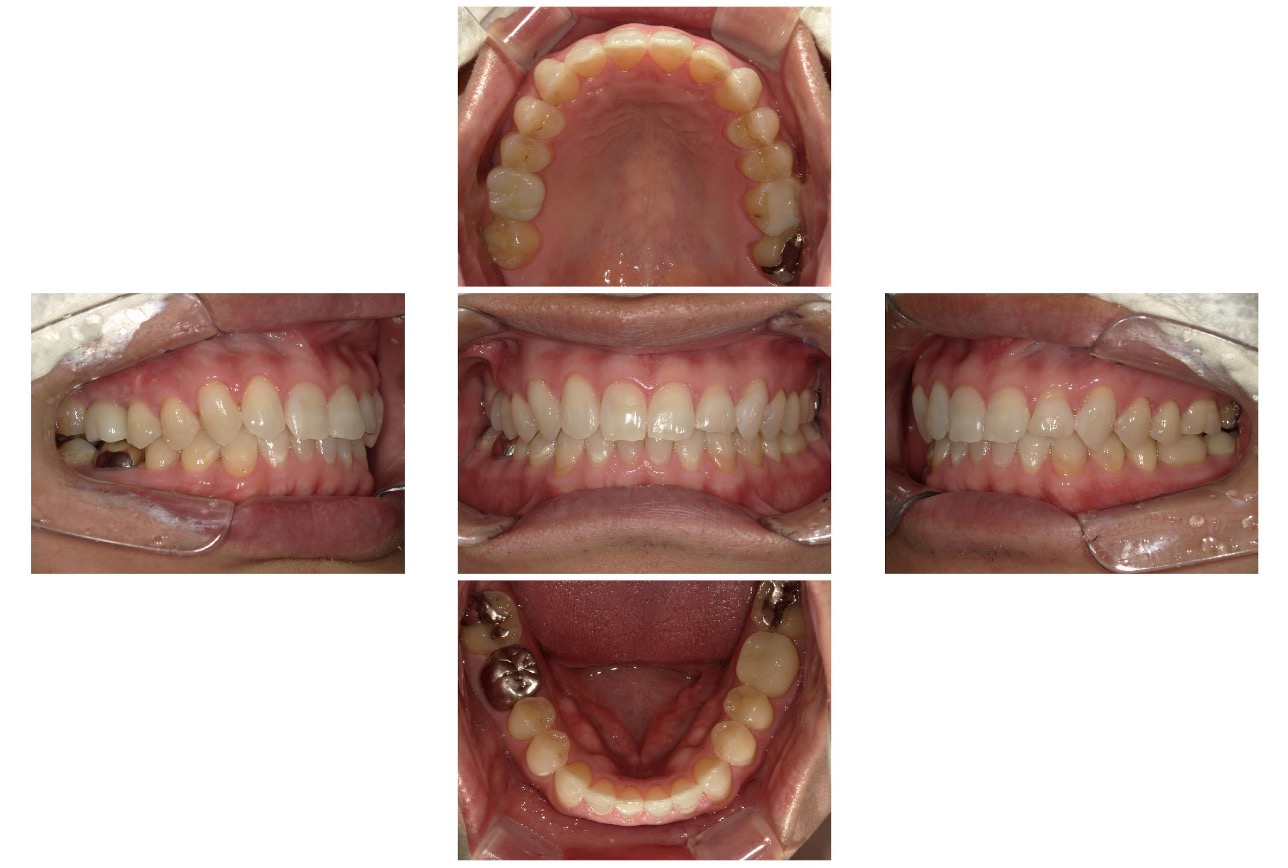

Case.01

治療前

治療後

| 主訴 | 前歯の歯並びが気になる |

|---|---|

| 治療 期間 | 約4か月 |

| 治療費 | 350,000円 (税込385,000円) |

| 治療 内容 | マウスピース(インビザラインGO)を装着して歯を動かします。 |

| 治療の リスク | 規定時間以上装着しないと、予定通りに歯が動かないことがあります。 |